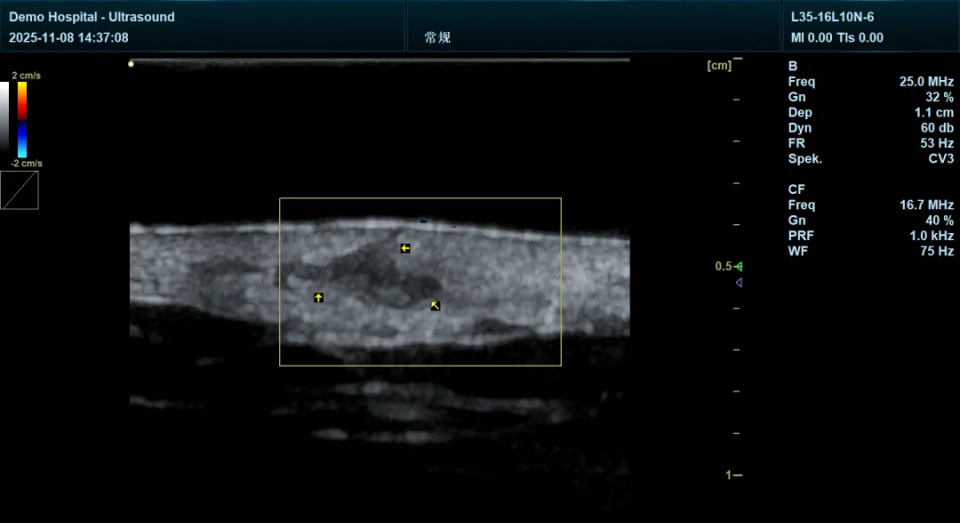

近日,在天府锦城实验室(未来医学城)前沿医学装备研究院,源自国家重点研发计划的高频皮肤超声成像技术正式进入临床验证阶段。该技术凭借高频率、阵元小间距的硬件突破,实现了对皮肤层次与皮下病变的“超清可视化”,为皮肤科临床诊断与治疗评估提供了全新工具,正推动皮肤诊疗走向“影像引导”的精准化新阶段。

当前,皮肤科诊疗仍高度依赖医生肉眼观察与病理活检,前者难以穿透表皮观察深层病变,后者则为有创操作且无法实时动态评估。针对这一现状,天府锦城实验室(未来医学城)前沿医学装备研究院基于在超声影像领域的技术积累,成功研发出新一代高频/超高频皮肤超声系统,其频率更高、阵元间距更小,可清晰显示皮肤各层结构、微小血管及附属器动态,显著提升图像分辨率和诊断信息量。

毛囊炎

“这项技术的核心突破在于频率高且阵元间距小,使得超声能够更精准地凸显病变的层次结构、大小、边界等信息,能为临床提供关键参考。”前沿医学装备研究院负责人表示,“我们希望通过无创、实时的影像方式,为皮肤病变的筛查、诊断与治疗随访提供可靠依据。”

在近期开展的多中心临床测试中,该设备已初步应用于皮肤肿瘤鉴别、炎症评估、术前规划等多个场景。参与测试的皮肤科医生反馈:“其成像清晰、操作直观,尤其在辨别皮损性质、评估治疗反应方面展现出显著价值,为临床决策提供了重要影像支持。”

作为天府锦城实验室(未来医学城)在医学影像领域的重要布局之一,高频皮肤超声技术不仅体现了实验室“临床需求驱动研发”的创新理念,也为皮肤科精准诊疗提供了新的技术路径。